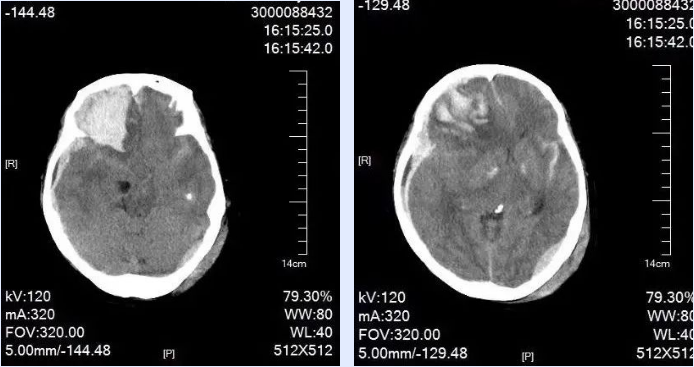

近日,接到有人晕倒摔伤的急救电话,我院急诊团队第一时间出发,将患者送达医院抢救。随后,以“重型开放性颅脑损伤;右侧额叶急性硬膜下血肿;右侧额叶脑挫裂伤;创伤性蛛网膜下腔出血;左侧枕部急性硬膜外血肿;颅底骨折伴脑脊液鼻漏;高血压病2级;腰1椎体、胸11、12椎体压缩性骨折”等症收住我院神经外科。

患者入院时已出现神志不清、嗜睡、言语含糊等情况。入院后不久,患者病情进行性加重,神志昏迷,呼吸急促,瞳孔不等大,对光反射迟钝,生命垂危,复查头颅CT,结果显示硬膜下血肿、脑内血肿出血急剧增多,中线移位明显,需立即行手术治疗。

时间就是生命,速度决定安危,准确研判患者伤情后,在麻醉手术科的配合下,我院神经外科贺喜武手术团队积极行手术抢救,术后,经ICU 20余天全力救治,患者最终转危为安。后期恢复远超预期,与摔伤前无异,神经外科团队高超的救治水平得到患者及家属的一致认可。